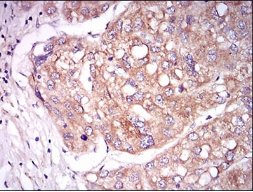

TIE1 Mouse Monoclonal antibody[8D12B]

Species Reactivity:    Human

IHC    1/200 - 1/1000